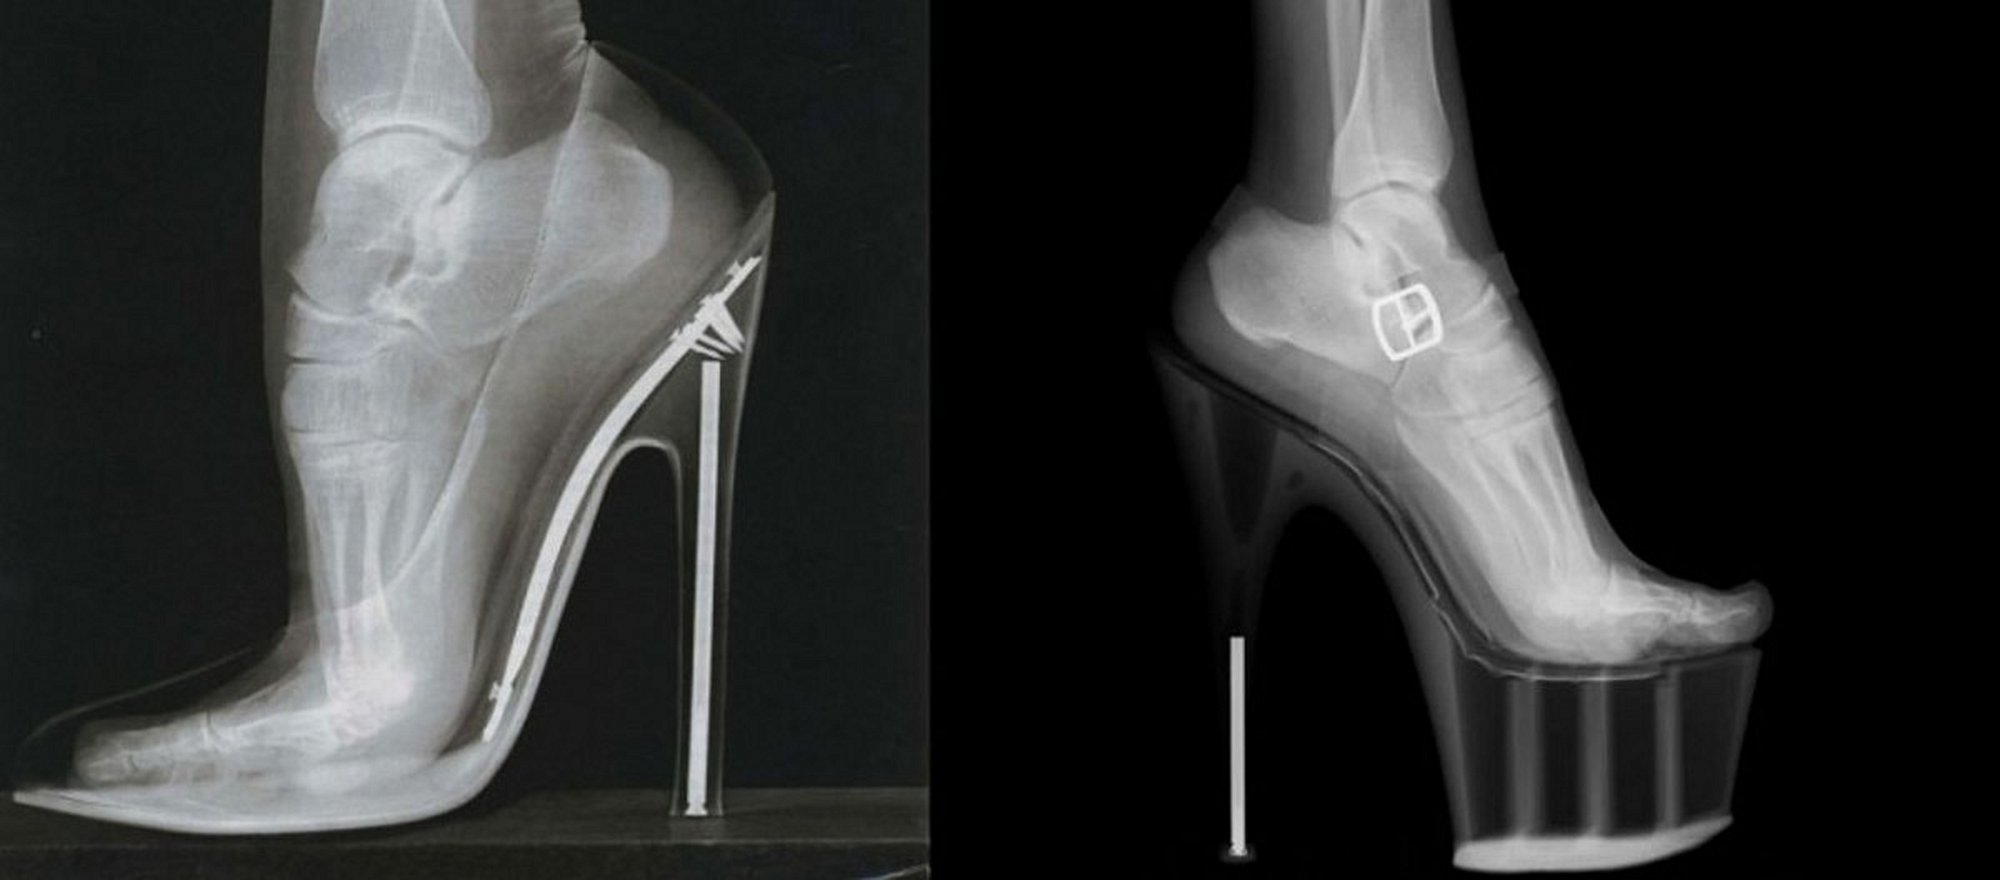

Yüksek Topuklu Ayakkabılar ve X-Işını Taraması

- Topuklu ayakkabılar insan anatomisine uygun olmayan ve uzun süre kullanıldığında iskelet ile kas sorunlarına yol açabilen bir moda aracıdır.

- Aşırı yüksek topuklu ayakkabıların uzun süreli kullanımı, ayaktaki Lisfranc eklemi çevresinde kemik aşınması ve kırıklara neden olan Lisfranc Kırılması veya Çıkığına sebep olabilir.

Her ne kadar modanın ve cinsel çekiciliğin bir aracı olarak görülseler de topuklu ayakkabılar, tahmin edebileceğiniz ve muhtemelen deneyimlemiş olabileceğiniz gibi, insan anatomisine kesinlikle uygun olmayan tuhaf bir ritüeldir. Çok uzun yıllar ve sürekli olarak anatominin buna zorlanması durumunda, ilerleyen yaşlarda rahatsızlık verici iskelet ve kas sorunlarıyla karşılaşılabilir. Kaldı ki, çoğu zaman, bu sorunların ortaya çıkması için fazla bir zaman geçmesine gerek de yoktur.

Dişilerin aşırı yüksek topuklu ayakkabıları uzatılmış süreler boyunca giymeleri sonucu oluşan kemik aşınması ve kırılmalarına Lisfranc Kırılması veya Lisfranc Çıkığı adı veriliyor. Lisfranc, çıkık ya da kırığın genellikle görüldüğü ayak eklemlerine verilen isimdir. Bu eklem, 9 kemiğin birbirine sıkıca bağlandığı bir bağ dokusudur.